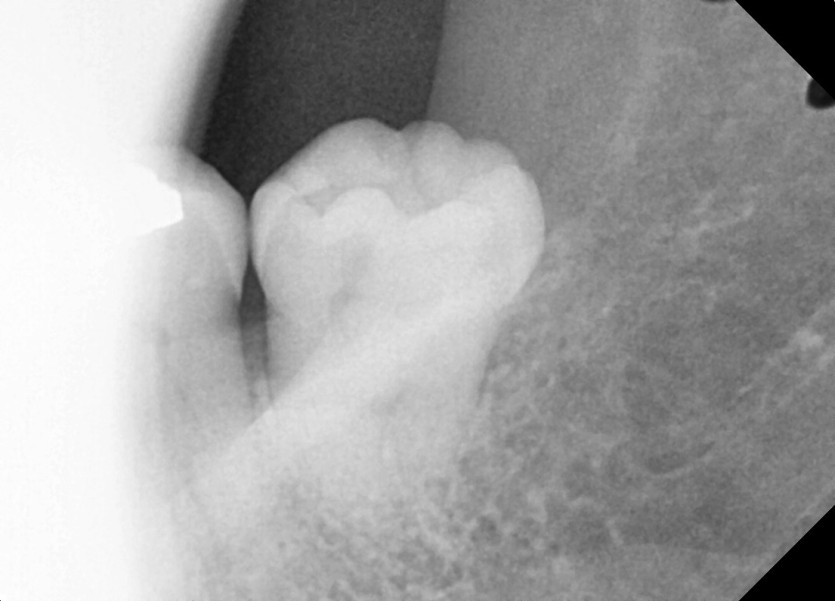

#38 사랑니 발치

구강 외과 전문의가 당일 발치했습니다.